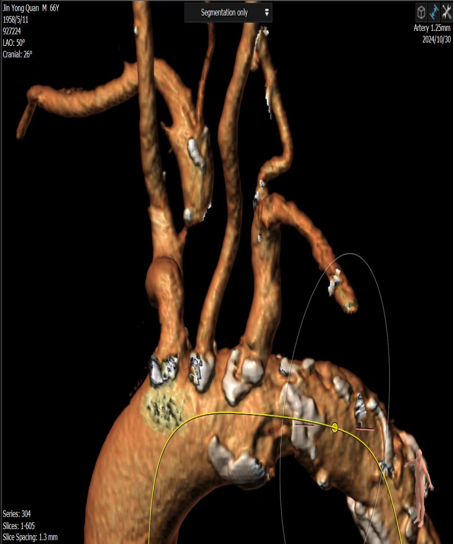

病例三

常规病变的精准支架释放:

即使是常规狭窄病变,采用CTA预定的角度(如 RAO 50° CRA 0°)也能实现支架的精准释放,确保完全覆盖病变且不影响重要分支。

图:CTA确定投射角度

图:支架精准释放

图:术中验证